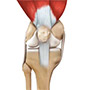

Ligaments of the Knee

Ligaments are tough bands of tissue that connect one bone to another bone. The ligaments of the knee function to stabilize the knee joint. There are two important groups of ligaments that hold the bones of the knee joint together, collateral ligaments and the cruciate ligament.

Collateral ligaments are present on either side of the knee. They function to prevent the knee from moving too far during side to side motion. The collateral ligament on the inside is called the medial collateral ligament (MCL) and the collateral ligament on the outside is called the lateral collateral ligament (LCL).

Cruciate ligaments, present inside the knee joint, control the back-and-forth motion of the knee. The cruciate ligament in the front of the knee is called anterior cruciate ligament or ACL and the cruciate ligament in the back of the knee is called posterior cruciate ligament or PCL.

Muscles of the Knee

Muscles: There are two major muscles, the quadriceps and the hamstrings, which enable movement of the knee joint. The quadriceps muscles are in the front of the thigh. When the quadriceps muscles contract, the knee straightens. The hamstrings are in the back of the thigh. When the hamstring muscles contract, the knee bends.

Tendons of the Knee

Tendons are structures that attach muscles to the bone. The quadriceps muscles of the knee meet just above the patella and attach to it through a tendon called the quadriceps tendon. The patella further attaches to the tibia through a tendon called the patella tendon. The quadriceps muscle, quadriceps tendon and patellar tendon all work together to straighten the knee. Similarly, the hamstring muscles at the back of the leg are attached to the knee joint with the hamstring tendon.